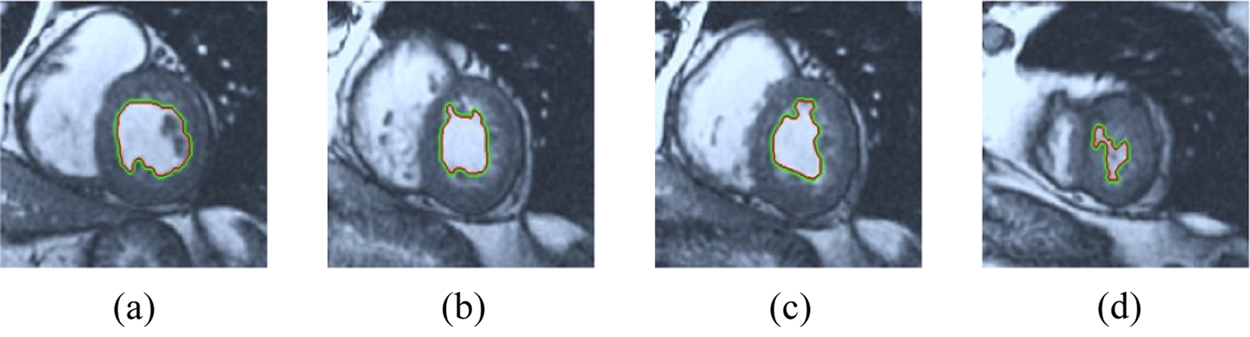

The BRW, HSRW, and ERW medical imaging segmentation schemes are executed on MATLAB, and examined on a short-axis of 3D multi-slices CMRI dataset [27]. Several segmentation performance metrics are utilized such as Dice Metric (DM), the Haussdorff distance (HS), and the Peak signal to noise ratio (PSNR). The BRW, HSRW, and ERW segmentation schemes are executed on a short-axis of 3D multi-slices CMRI datasets. The same multilayer CMRI dataset is segmented using various random walk methods. The presented results were obtained through using BRW, HSRW and ERW methods on five different groups of patients; each group contains 25 subject of multilayer CMR dataset. Experimental results illustrate that the BRW method can achieve a good segmentation of the LV cavity. The results of the HSRW algorithm have very comparable similarities to BRW, but with a slightly less efficiency and a much higher execution rate. Pre-calculations reduce the performance online time in offline mode. The average time of HSRW equals to 0.09 seconds for each slide. Raising the rate of K will improve the comparison and makes the process of segmentation more precise, but also reduces the execution time. The ERW technique results illustrate that this method has the greatest efficiency of segmentation. Figs. 5 to 7 show the resulting images of the BRW segmentation method on five sets of sample data. HSRW with pre-calculation segmentation method is applied on the same sets of sample data and illustrated in Figs. 8 to 10. Figs. 11–13 show the high efficiency segmentation using the ERW method with an earlier model for the same sets of sample data. The results of the Random Walk segmentation overcame the potential restrictions of the prior art CMR methods. The performance of segmentation is fast compared to segmentation methods based on edge and region. BRW precedes into account the properties of regions and edges, as shown in Figs. 5–7. Looking at the image as a graph, the technique makes it possible to integrate pixel relations with neighboring pixels. As a result, segmentation produces good quality BRW technique sections when their qualitative accuracy is compared to the ground truth, and this is also evident from the Tab. 1 measurements in the diastolic and systolic phases in Tab. 2 as well as in the complete cardiac cycle noticed. Figs. 8–10 illustrate the HSRW results. There are no dissimilarities observed in furthermost cases of CMR slides in the figures, but the correspondence measurements of the DM, PSNR and HS coefficients present that the results of the HSRW technique are worse than those of the BRW method. This presents that HSRW is an effective estimation of the random walk influence as mentioned in Tab. 1 and throughout the cardiac cycle in Tab. 2. The values of PSNR and DM are lower, whereas HS is higher than the BRW method, but with slight dissimilarities between HSRW and BRW methods throughout the blood circulation. The impact of execution eigenvectors pre-calculations is perfect when the execution time is faster than the BRW method and, in fact, more efficient than other segmentation method for LV heart segmentation. With the identical dataset, the ERW method shows a significant enhancement in efficiency, as presented in Figs. 11–13. From the scores, we can see that the segmentation is smoother and cleaner. The ERW method considers boundaries and areas, such as BRW, using the relations between adjacent pixels in the image. It also considers the additional regional advantage by including the assumptions that affect the results of the segmentation. Mean segmentation quality measurements are computed from the segmented images using correspondence measurements for instance DM, HS, and PSNR and verified for each method in the diastolic and systolic stages as presented in Tab. 1. Based on results, it can be determined that methods of random walk are enhanced in diastolic diagnosis and that their outcomes in the systolic stage are also of good efficiency. The results of the random walk segmentation methods in the complete blood circulation are shown in Tab. 2. The cardiac cycle similarity amounts indicate that DM and PSNR capacities of ERW are improved than the corresponding capacities in the case of the HSRW and BRW approaches; however, the HS measurements are lower than the equivalent measurements, as illustrated in Tab. 2. This designates that the ERW technique is the furthermost accurate segmentation technique among all the approaches stated above. The ERW technique has the uppermost value of PSNR, and the HSRW method has the lowermost value that denotes the uppermost speed in segmentation process.

Figure 8: HSRW results for the first samples set

Figure 9: HSRW results for the second samples set

Figure 10: HSRW results for the third samples set